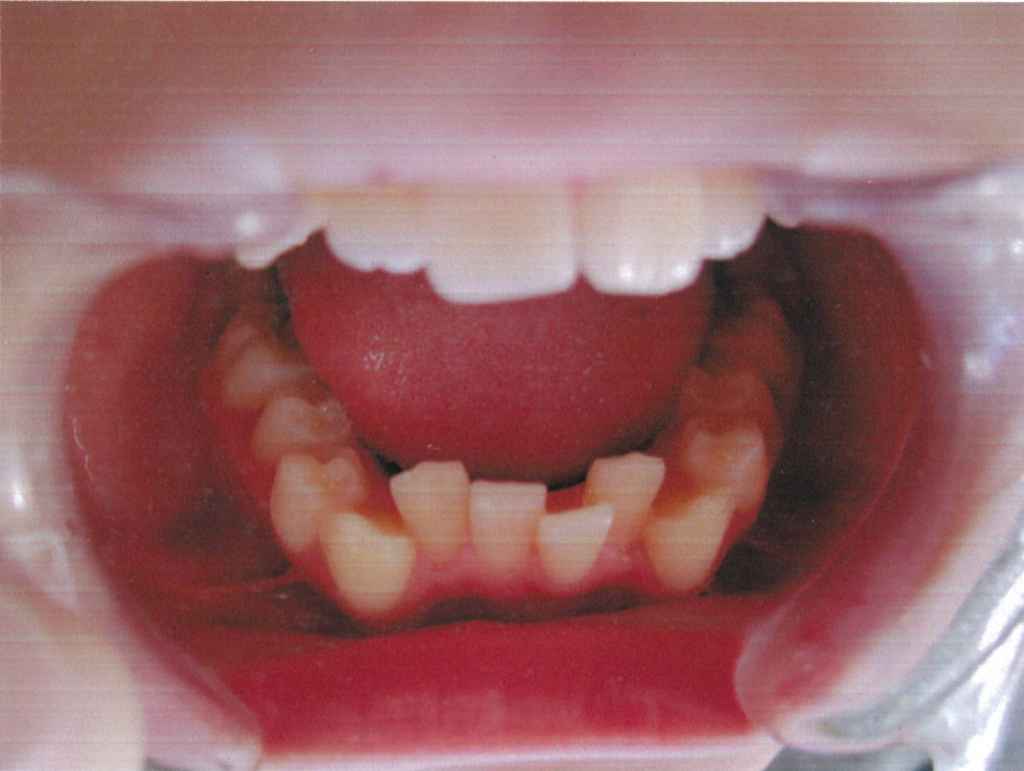

現代の子ども達は、よく調理されたやわらかいものを食べることが多く、それに伴い、あごの発達が悪くなり、歯の大きさに対して、あごの大きさが小さく、スペースがないために前歯がデコボコになったり、その後ろに生えてくる犬歯(前から3番目の歯)が生えるスペースを失い、外側に生えてしまう八重歯という歯並びになりやすいのです。

永久歯になってからでは(小学校高学年から中学校1、2年)、子ども達の成長期のピークを過ぎていることが多く、歯を抜いて矯正する頻度が増えてしまいます。

床矯正装置は、つけることによって、口の中を毎日拡大していくことができ、あごの発育を助け、永久歯が綺麗に生えるスペースを確保し、綺麗な歯並びを作ることができるようになります。また、しっかりとしたあごをつくることで、健康で充分な成長発育を促す助けとなるものと考えています。

『良い歯並び』とは、真っ直ぐに生えることの他に、生えるスペースがあるかということも大変重要です。『矯正=抜歯』のイメージがありがちですが、豊歯科で行っている矯正は、正しいあごの大きさに骨格を整える『床矯正』といい、永久歯がキレイに並ぶように土台を作ってあげることを目的としています。